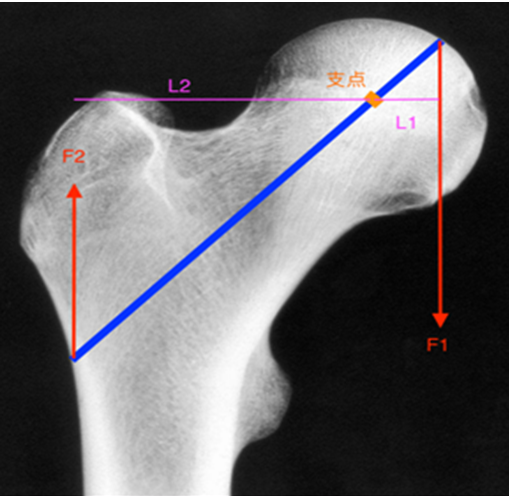

在与临床专家深入交流中发现,更复杂、更不稳定的骨折类型,仍需更优的力学解决方案。这催生了从“器械改良”到“理论创新”的飞跃。基于“杠杆-支点重建”理论研发的PFBN成为破局的关键。它在股骨近端内部构建了一个独特的双三角支撑结构,通过拉力螺钉与张力螺钉在三维空间形成交叉锁定,实现了仿生学意义上的力学重建。瑞鹤医疗获得了这一创新产品的授权,此产品已于2023年6月正式获得国家药品监督管理局批准上市,标志着其从理论到临床应用的坚实落地。

“这不仅仅是多了一颗钉子。”参与转化研发的工程师表示,“它通过三角支撑固定,将应力从传统的‘集中承受’变为‘立体分散’,相当于在骨折端内部搭建了一个稳定的‘脚手架’。”生物力学测试表明,该设计能将关键区域的应力峰值降低数倍,理论上能显著减少螺钉切割、髋内翻等并发症,代表了当前此领域设计理念的重要突破。

在PFBN的医工结合经验基础上,瑞鹤医疗的研发再次向前沿深探。“股骨近端髓内钉系统”PFLBN、PFTBN,应用了原创性“杠杆平衡重建理论”,在结构设计和材料力学上实现了进一步优化。2025年8月20日,该系统通过国家药品监督管理局创新医疗器械特别审查。官方信息指出,其“力学性能较同类已上市产品具有显著提升,在技术上达到国际领先水平,预期可有效减少术后股骨颈短缩、髋内翻畸形等相关并发症的发生”。